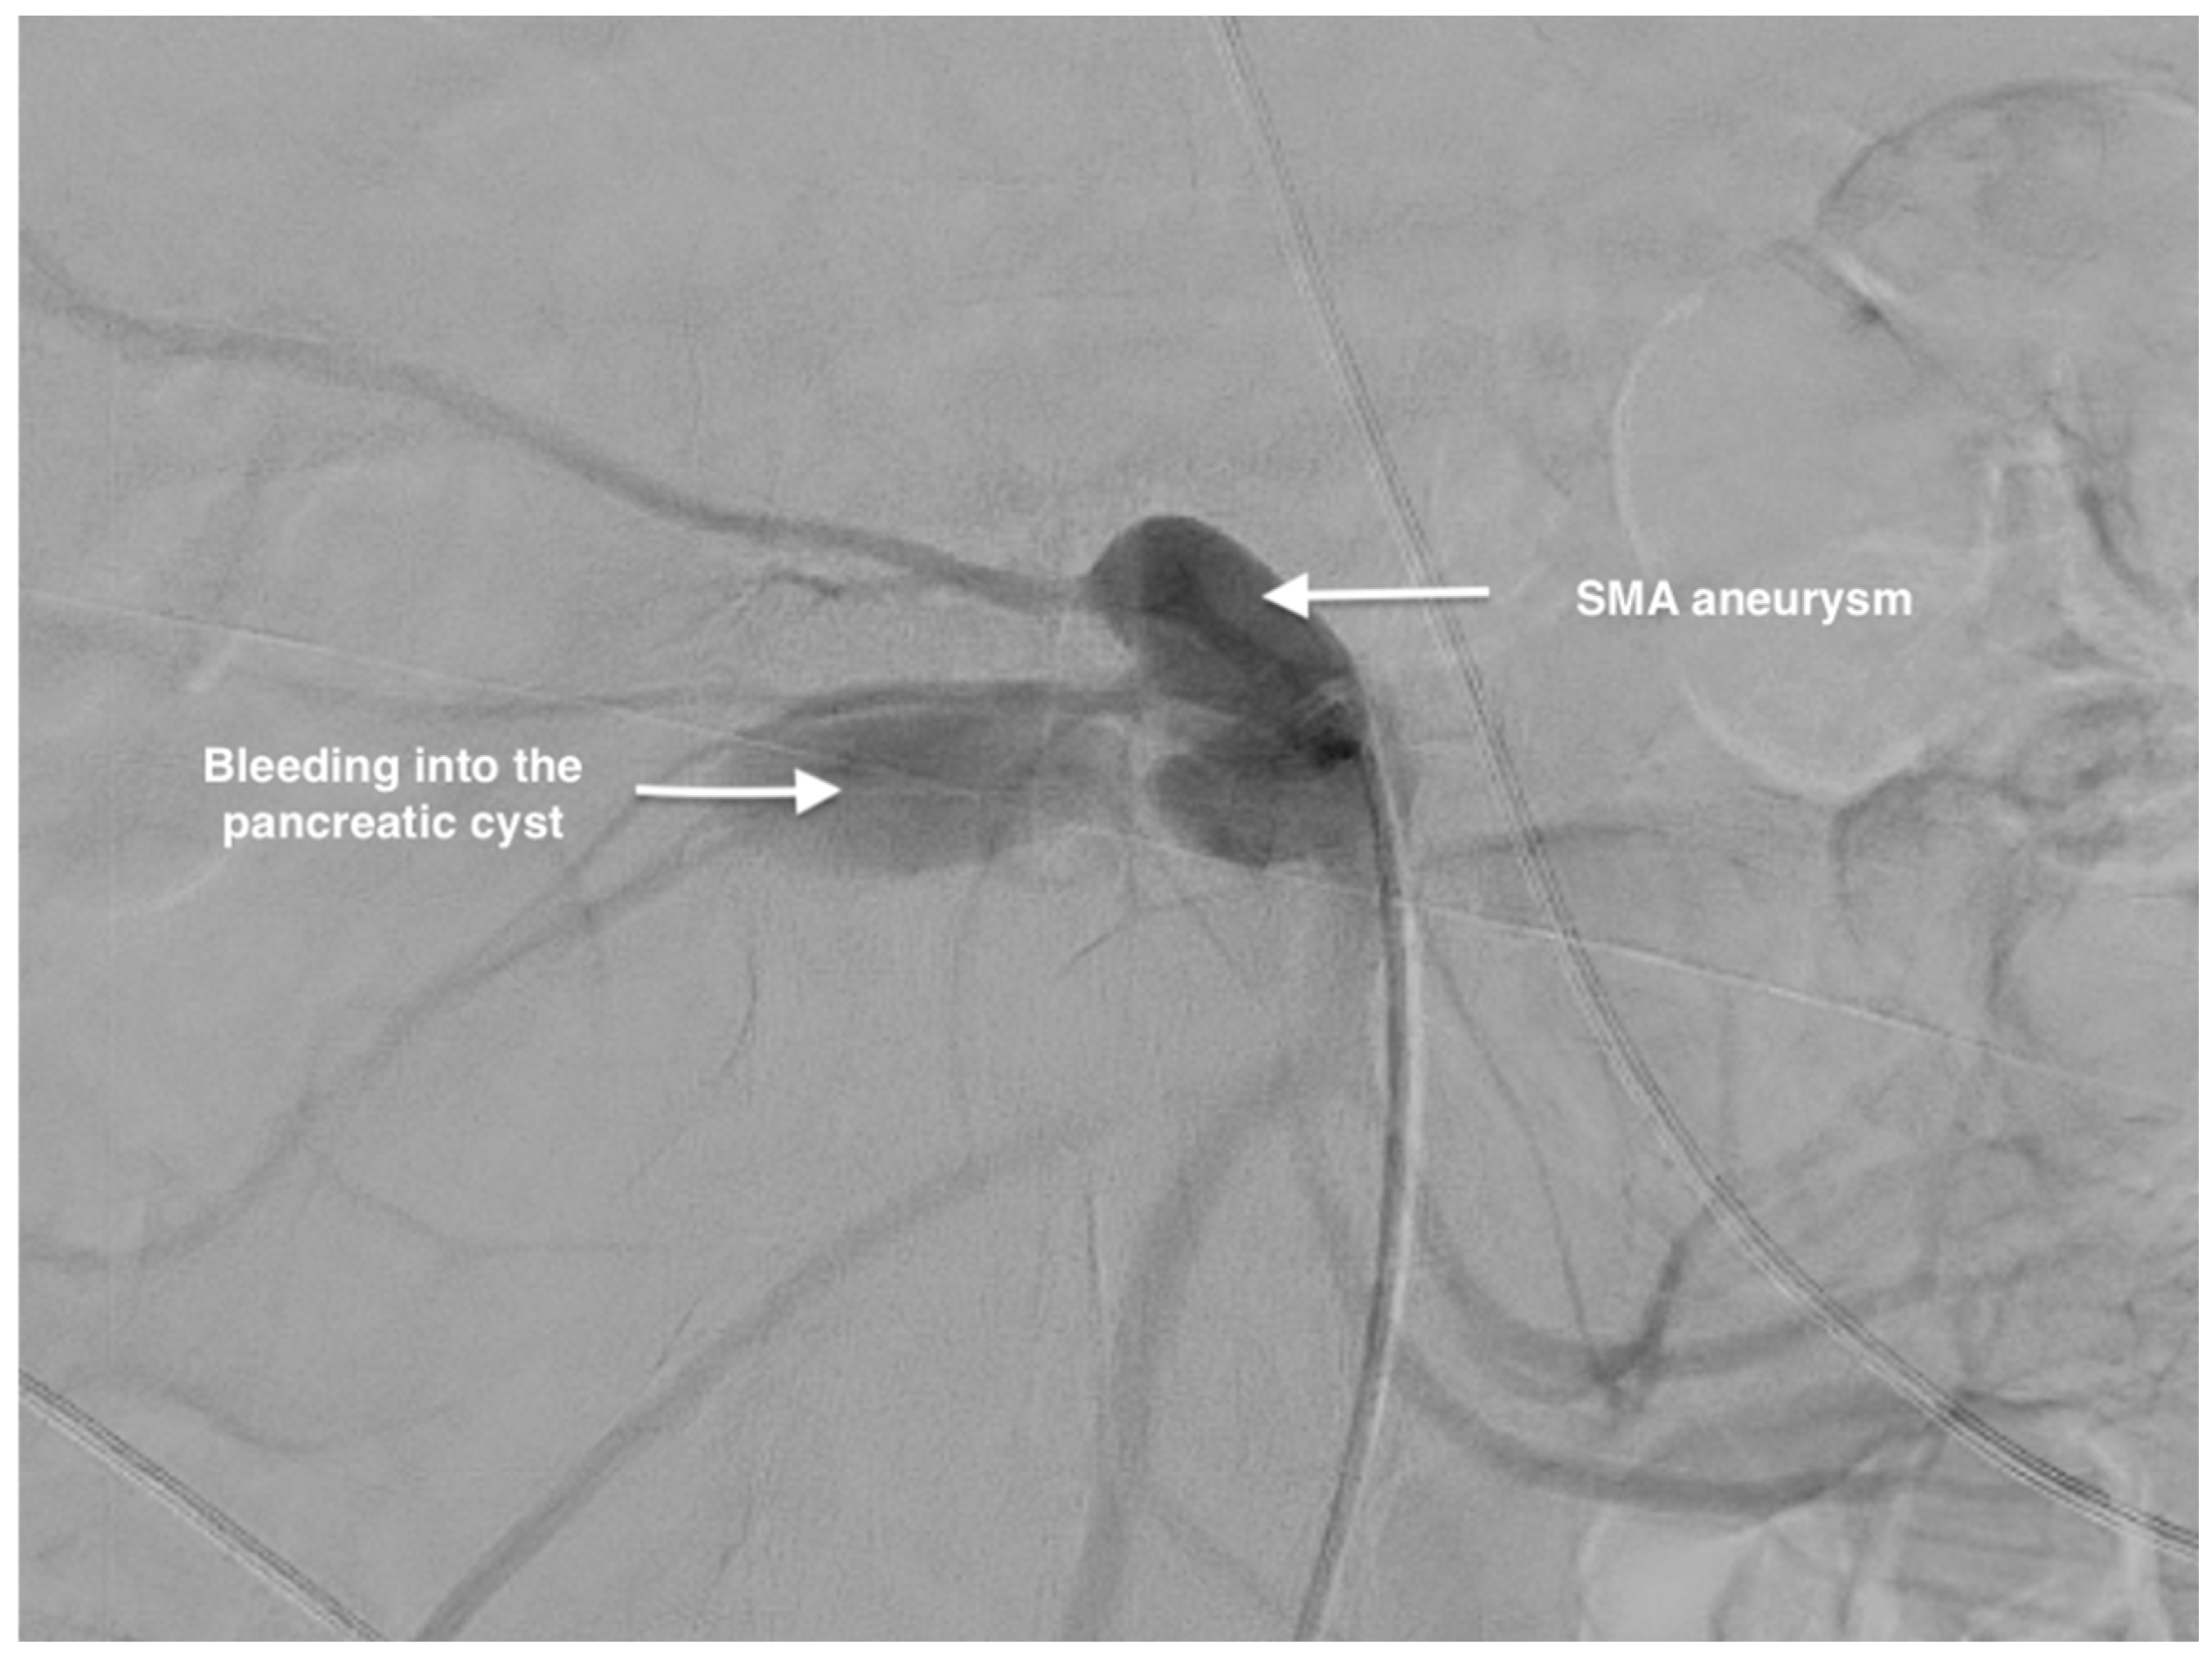

Management of a Rare Case of Superior Mesenteric Artery Aneurysm Associated with a Pancreatic Cyst Complicated by Acute Rupture: A Case Report and Review of Literature

2. Case Report

Surgical Technique